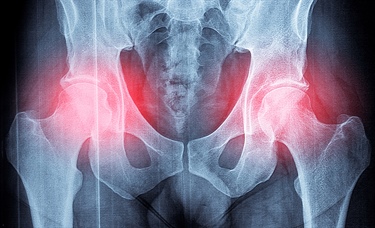

Gabapentinoids may raise risk for hip fracture

Nearly 5% of U.S. adults were prescribed a gabapentinoid in 2021, up from 4% of adults in 2015, a 17.5% increase in prescriptions over a 6-year period.